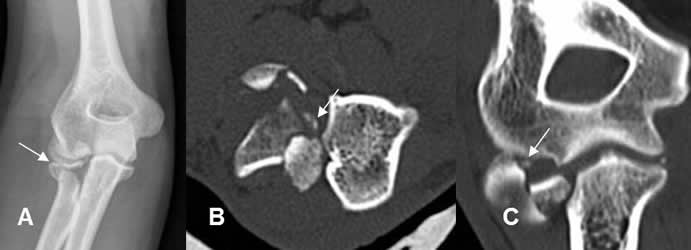

Fig 19. Fractura del codo.

A: Rx AP. Fractura en la cabeza del radio.

B: TAC axial. Fractura conminuta del radio, con varios fragmentos sueltos.

C: TAC reconstrucción coronal. Cuerpo libre intra-articular.